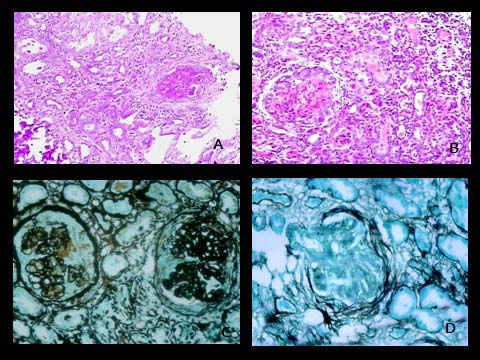

Specimens were subjected to light microscopic studies (with Hematoxylin and Eosin, periodic Schiff, Massons Trichrome and periodic methenamine silver). Autoimmune panel was employed in 79 cases. All the findings were noted and tabulated.

Specimens were subjected to light microscopic studies (with Hematoxylin and Eosin, periodic Schiff, Massons Trichrome and periodic methenamine silver). Due to economic constraints immunofluoresence studies were done wherever possible. Biopsy samples were considered satisfactory for diagnosis if they contained five or more glomeruli. Biopsies were categorized as inadequate for diagnosis if glomeruli were less than 5. A total of 3 pathologists reviewed and reported the histopathological slides over this period to limit the interpersonal bias. The final diagnoses were then tabulated to ascertain the spectrum of glomerular diseases.